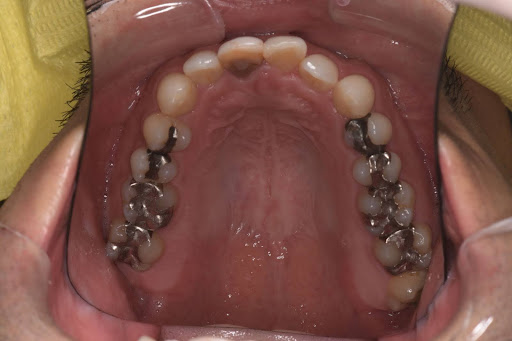

以下は症例写真です。

長年使用していた金属の詰め物を、生体親和性の高いセラミック素材に置き換えました。

天然歯のような透明感が生まれ、金属アレルギーの不安も解消されています。

<Before>